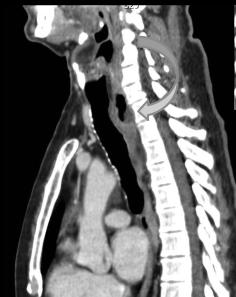

chaussette . Image TDM en fenetre parenchymateuse pulmonaire

,se donne des images si net de oesophage en coupe axiale ,

sagitale et de frontale ( voie image )

Image Achalasia de oesophage en

coupe TDM sagitale |

Meme cas en coupe TDM frontale ( coronale

) . |